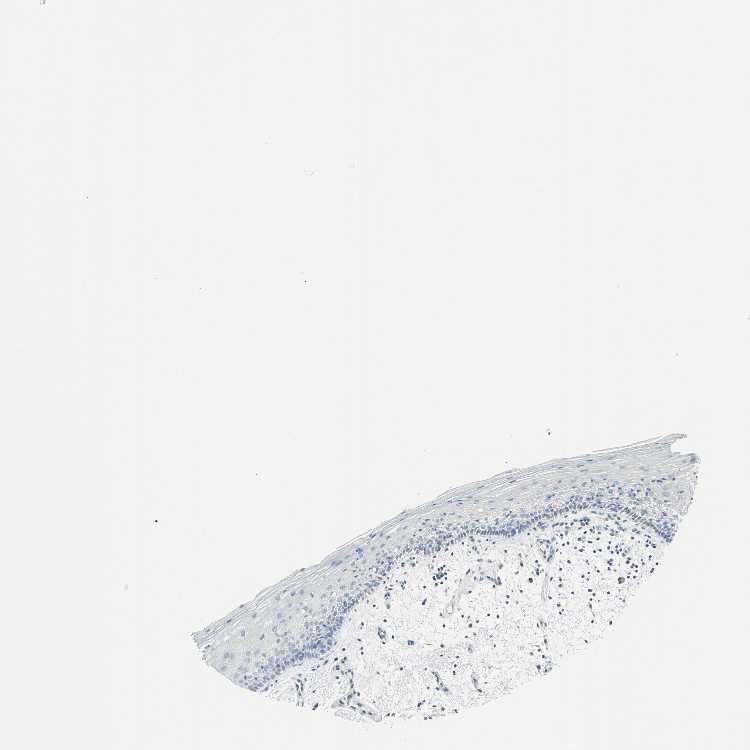

TISSUE PRIMARY DATA ORAL MUCOSA Show tissue menu

ORAL MUCOSA - Antibody stainingi

Antibody staining in the annotated cell types in the current human tissue is reported as not detected, low, medium, or high, based on conventional immunohistochemistry profiling in selected tissues. This score is based on the combination of the staining intensity and fraction of stained cells.

Each image is clickable and will lead to virtual microscopy that enables deeper exploration of all samples and also displays staining intensity scores, fraction scores and subcellular localization as well as patient and tissue information for each sample.

Antibody HPA017919Antibody HPA019649Antibody HPA027734Antibody CAB006246

Squamous epithelial cells Not detectedHighLowNot detected